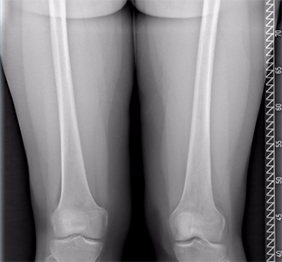

Radiografie cu stitching

Este o metoda radiologica de reconstructie a imaginilor obtinute, pentru a permite o vizualizarea cat mai exacta si precisa fie a membrelor inferioare, fie a coloanei vertebrale in intregime.